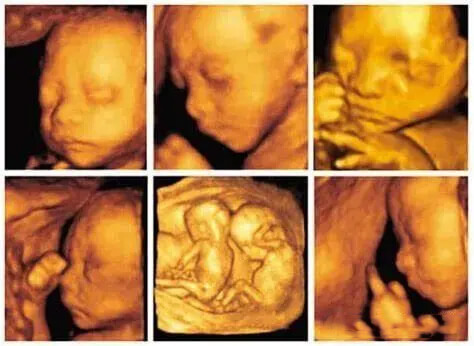

孕妇在孕期22到26周要进行排畸筛查,会进行一次四维彩超检查,可以打印出来四维彩超图片,因为彩超图只有明暗黑白,和真实照片有很大区别,所以我们很难看出宝宝的样子。

而我们就可以通过AI绘画技术,根据彩超图中宝宝的脸型,头型,五官位置等信息,利用人工智能算法,可以大致预测并画出宝宝的样子。

上传宝宝思维彩超图,最好是正面图